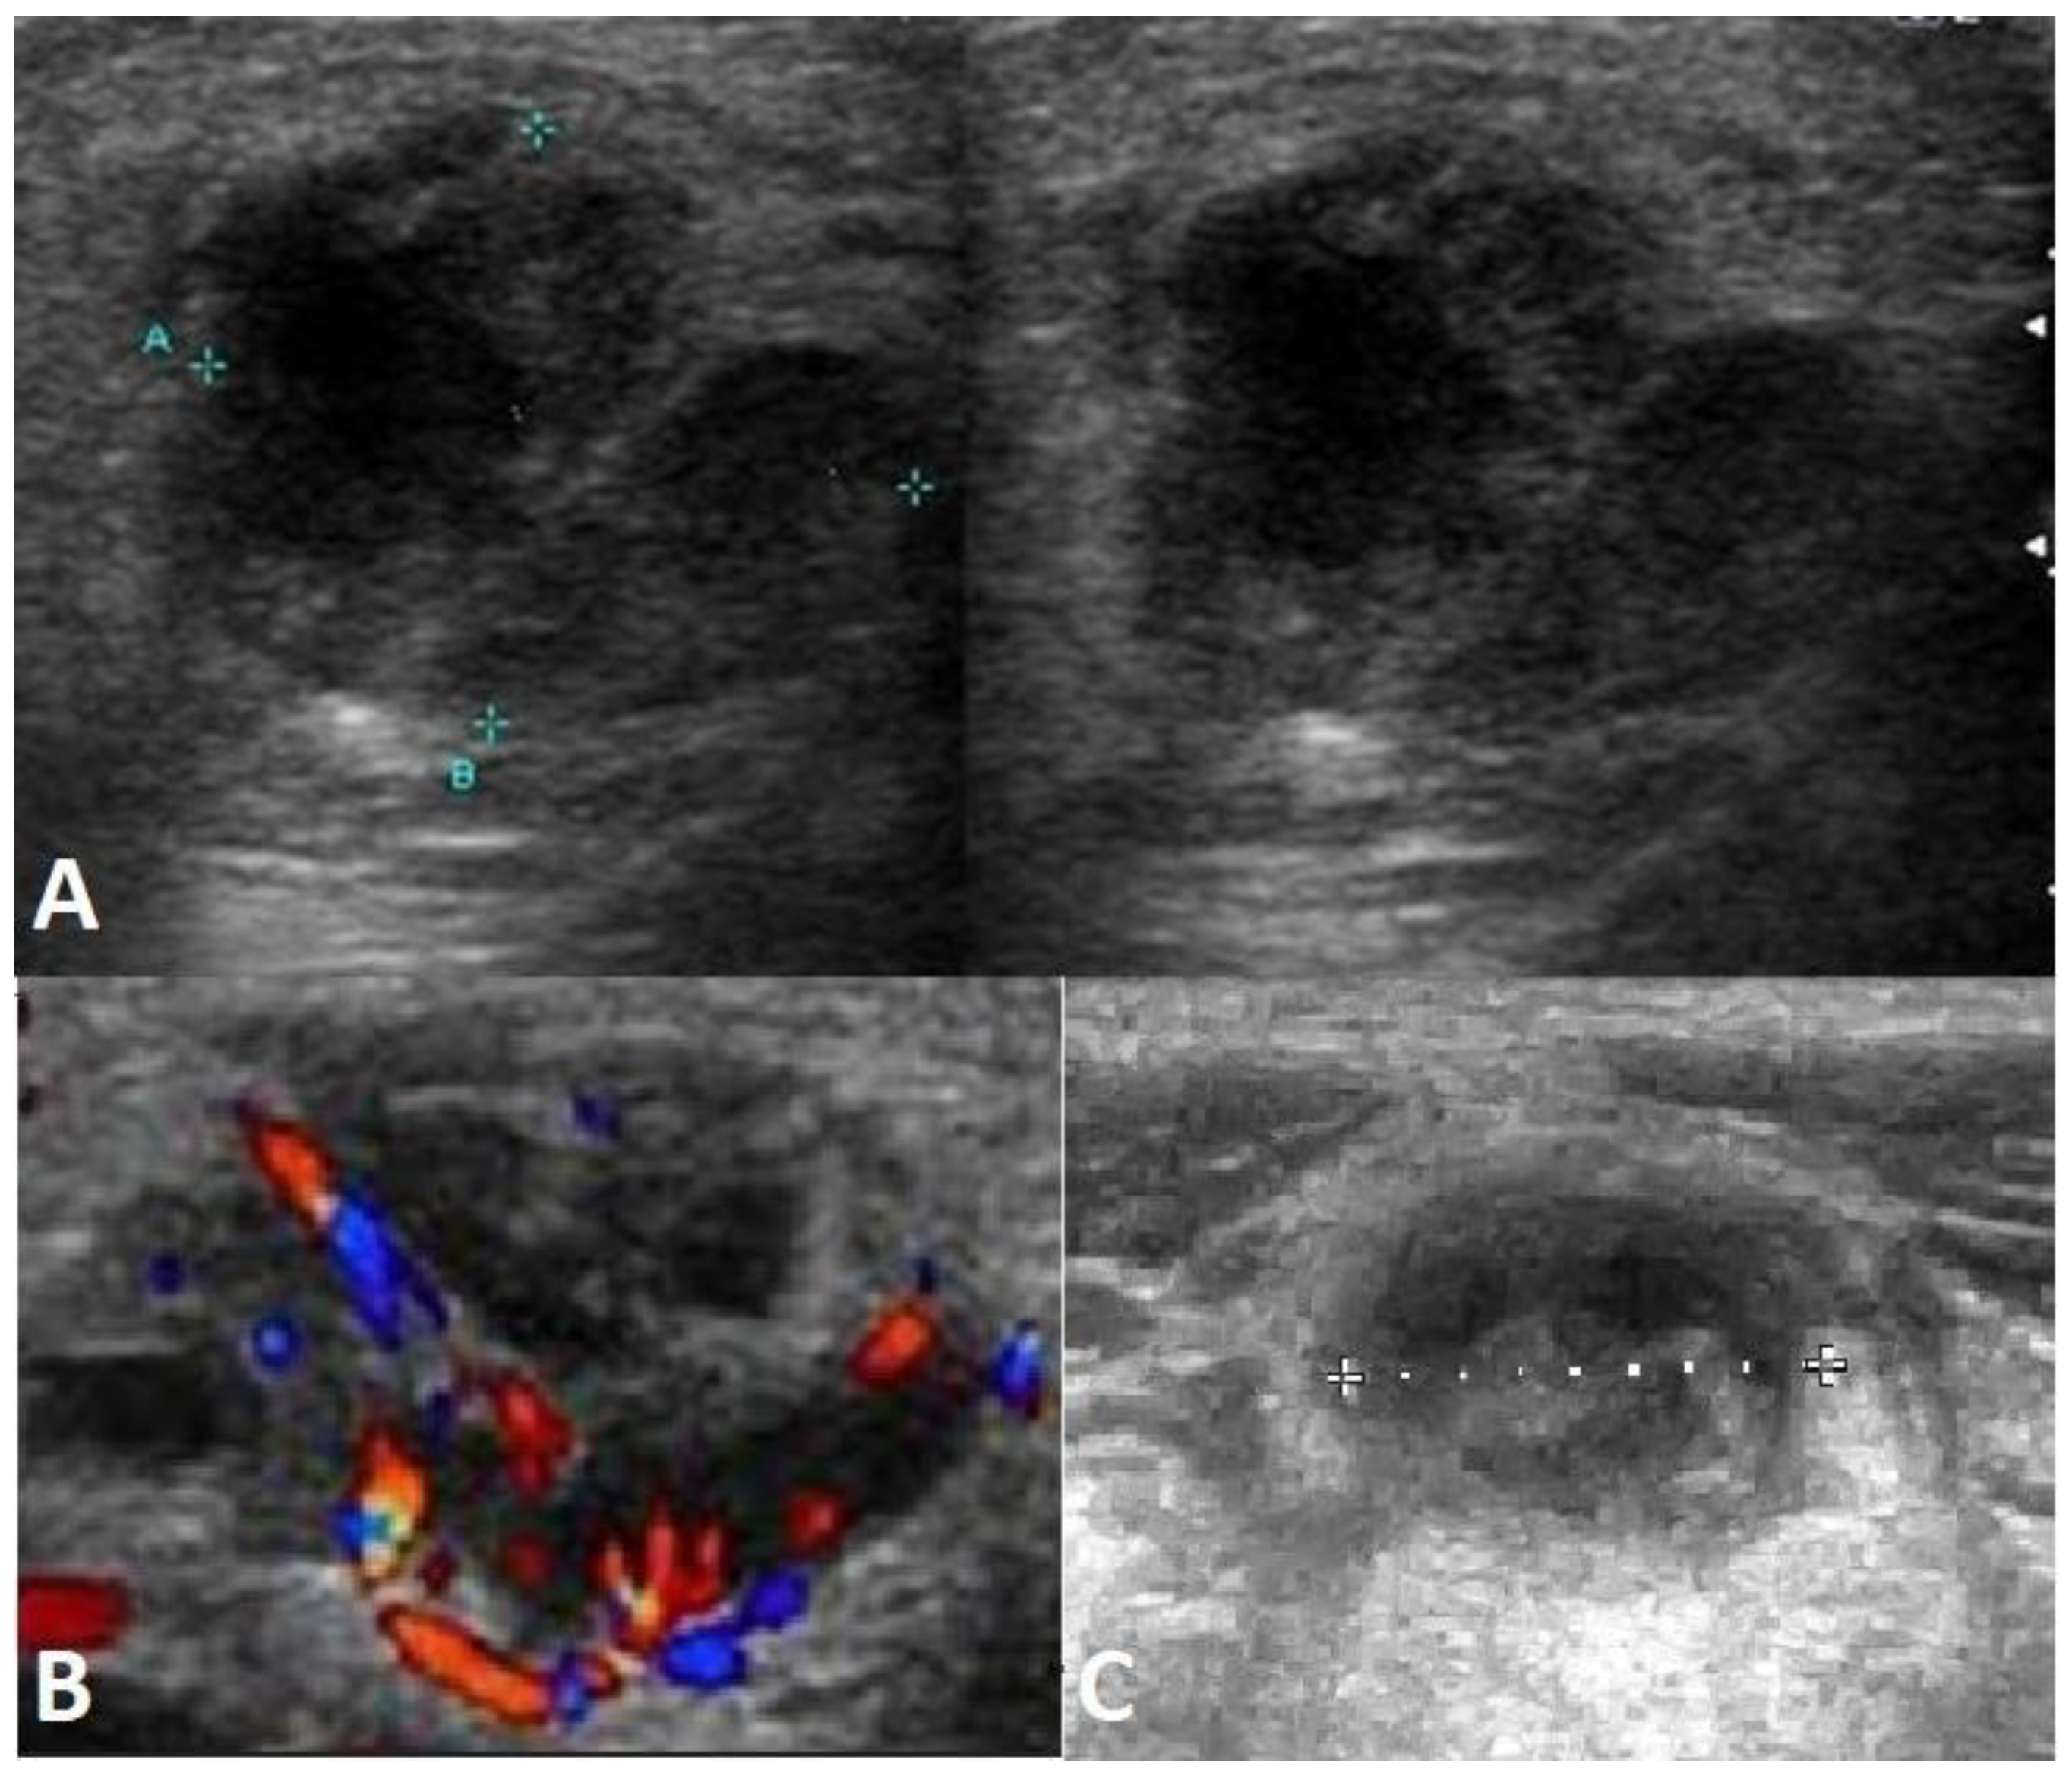

- Jończyk-Potoczna, K.; Potoczny, J.; Szczawińska-Popłonyk, A. Imaging in Children with Ataxia-Telangiectasia—The Radiologist’s Approach. Front. Pediatr. 2022, 10, 988645. [Google Scholar] [CrossRef] [PubMed]